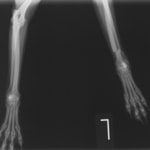

橈尺骨骨折 : 症例1 | 症例2 | 症例3 | 症例4 | 症例5 | 症例6 | 症例7

: 症例8 | 症例9 | 症例10 | 症例11 | 症例12 | 症例13 | 症例14

: 症例15 | 症例16 | 症例17 | 症例18 | 症例19 | 症例20 | 症例21

Locking Compression Plate

LCPは、スクリュー(ネジ)とプレート(金属の板)をロックする特殊な構造により骨折部位を固定する新しい世代のプレートシステムです。ひとつのホールでロッキングスクリューとスタンダードスクリューの使用を選択できるユニークな構造をしているため、骨折断端間の圧迫を目的とした従来型プレート固定法に加え、高い角度安定性を有するロッキングスクリューを用いた固定法の選択が可能です。従来のプレートシステムでは困難だった部分の骨折や癒合不全の症例に高い治療効果をもたらします。

Locking compression plate system の特徴

1.骨膜上の血行障害は最小限

2.高い角度安定性

3.プレート設置時の整復位喪失の防止

4.スクリューのルースニング(ゆるみ)の防止

5.コンビネーションホール

6.粗鬆骨における固定性の向上

7.1.5mmと薄いプレートのため、超小型犬にも使用しやすい

8.抜去が不要となることが多い